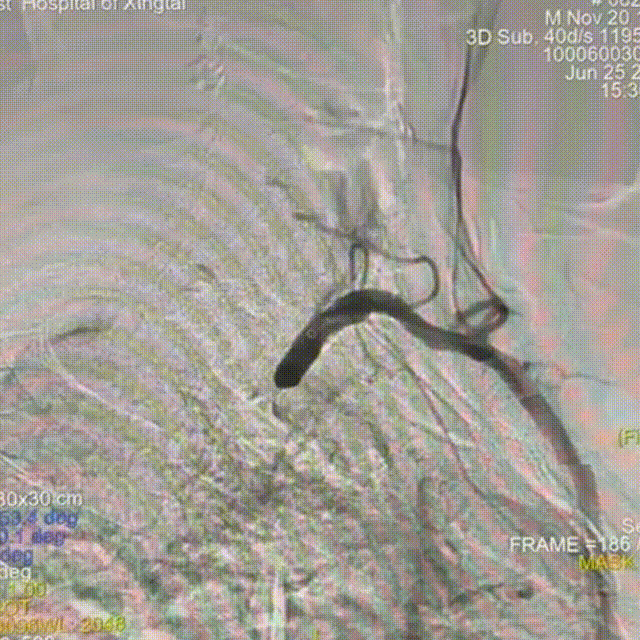

术后即刻造影

狭窄解除,前向血流好转。

动脉长鞘怎么置入【有励可说】Locaste 088长鞘经左桡治疗左侧锁骨下动脉狭窄一例_https://www.jmylbn.com_新闻资讯_第15张

狭窄解除,盗血消失。